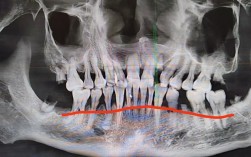

看到你关心正畸后的牙槽骨吸收问题,我能理解这种担忧,正畸治疗确实可能伴随牙槽骨的吸收变化,但请别太担心,这通常是正常过程的一部分,关键在于区分生理性和病理性吸收,让我来详细解释一下X光片上如何表现、原因以及应对方法:🦷一、牙槽骨吸收在X光...